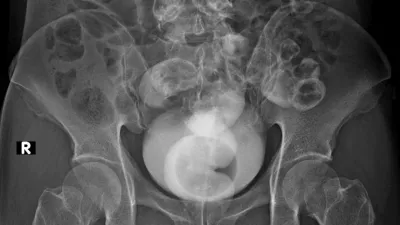

Diagnoza je bila neizprosna: descensus oziroma zdrs medeničnih organov. Njen mehur, maternica in danka so izgubili oporo in se povesili v vaginalni kanal. Spoznanje je bilo šokantno, toda za statistiko presenetljivo običajno.

To namreč ni osamljen primer. Ocenjujejo, da se bo kar 40 odstotkov žensk v svojem življenju srečalo z neko obliko zdrsa medeničnih organov. Gre za stanje, pri katerem podporna tkiva medeničnega dna – mišice in vezi, ki delujejo kot viseča mreža za organe – popustijo. Posledica je zdrs enega ali več organov (mehurja, maternice ali črevesja) navzdol proti vaginalni odprtini.

Rentgenska (simbolična) slika / Foto: Istock

Rentgenska slika / Foto: Istock